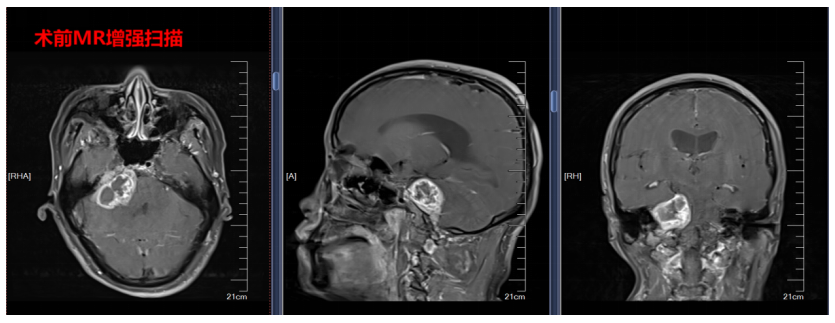

吴女士术前检查影像

另一位54岁的患者吴女士,因听力下降伴抽搐入院,经检查,其肿瘤位于生命中枢脑干旁的桥小脑脚区,手术风险极高,极易损伤重要颅神经。为此,医院迅速进行多学科会诊,借助多模态融合技术为患者制定手术方案,同时,医院整合影像、电生理等多平台资源,为手术提供全面支持。